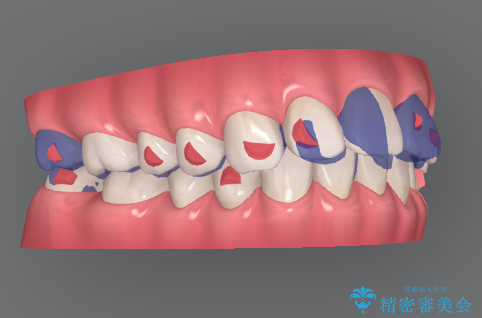

- インビザライン

- 8ヶ月

- 2-5回

費用と期間を相談し、「気になっているのは前歯だけ。」とのことでしたので前歯のがたつきのみをインビザラインで改善する矯正治療の計画を立てます。

しっかりとマウスピースの装用時間を守っていただき、非常にスムーズに治療を終了することができました。